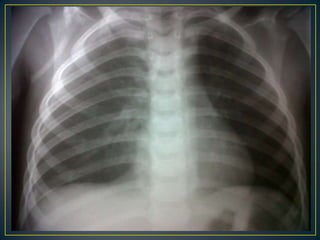

RxToraxPosteroanterior.9 EICRCT 54%Parénquima pulmonar con aumento de trama vascular y evidencia imagen radiopaca que borra seno cardiofrenico derecho.Estructuras óseas y blandas normales.USG ABDOMINAL.Derrame pleural bilateral.Esplenomegalia.Proceso renal agudo.Liquido libre en fosa de morrison, espacio yuxtaesplenico  y fosas ileacas.

21/8/11. EVOLUCIONPaciente hasta el día de hoy afebril, a quien se ausculta soplo tubarico y roncus en campo pulmonar derecho, se reevaluaRx de torax con imagen radiopaca  a nivel de seno cardiofrenico que corresponde a neumonía con tendencia a la consolidación por lo que se decide iniciar tratamiento con acetilcefuroxima, se realiza frote periférico para descartar proceso séptico, se considera que hepatomegalia sea por el proceso neumónico; sin embargo esta 2cm PDRC  que no es significativa.

Transaminasas: En algunos casos están elevadas.Ionograma: Hiponatremia.Urea: Elevada.Proteínas Totales: Hipoproteinemia.Complemento sérico: Está disminuido el Clq, C4 y C5- C8, con aumento del ritmo catabólico de C3.Electrocardiograma: Taquicardia o bradicardia, trastornos de repolarización y de la conducción aurículoventricular, con bloqueos de 1er y 2do grados.Rx. de Tórax:   Reforzamiento de la trama broncoalveolar, y derrame pleural bilateral o derecho.USG: Ascitis, hepatomegalia y edema perivesicular. (8)Gasometría: Usualmente existe acidosis metabólica. (12)Pruebas específicas para dengue    Similares a FD (6)